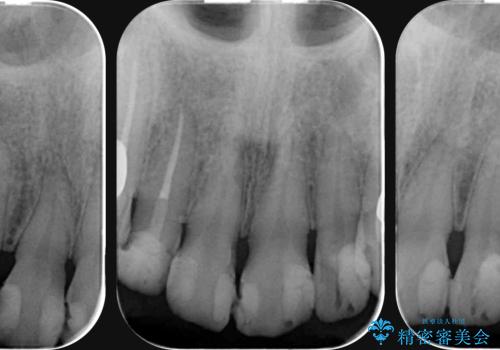

- 放置した虫歯の歯がボロボロになってしまい治療を希望され来院されました。

残根状態の歯、神経まで虫歯が達し失活した歯、歯肉縁下まで及んだ虫歯が多数認められます。

まず虫歯を拡大鏡、マイクロスコープ下で丁寧に取り除き歯肉縁下の虫歯を歯周外科により解決したのち、ジルコニアクラウン製作を行っていきます。